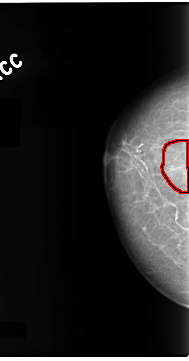

C_0099_1.RIGHT_CC

LEFT_CC LINES 4744 PIXELS_PER_LINE 2352 BITS_PER_PIXEL 12 RESOLUTION 50 NON_OVERLAY

FILE: C_0099_1.RIGHT_CC.OVERLAY

TOTAL_ABNORMALITIES 1

ABNORMALITY 1

LESION_TYPE CALCIFICATION TYPE PLEOMORPHIC DISTRIBUTION CLUSTERED

ASSESSMENT 5

SUBTLETY 5

PATHOLOGY MALIGNANT

TOTAL_OUTLINES 1

BOUNDARY